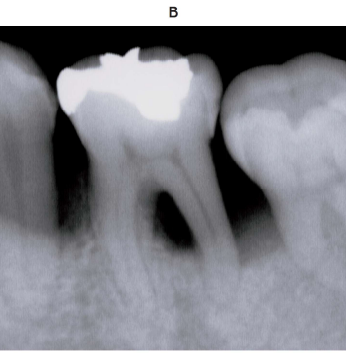

41 歳の女性。上顎左側前歯と小臼歯部の審美不良を主訴として来院した。 6 か月前から気付いていたがそのままにしていたという。角化歯肉の幅は上顎左側犬歯において 1 mm 程度である。歯周基本治療後の再評価時の口腔内写真(別冊No. 19A)とエックス線画像(別冊No. 19B)を別に示す。歯周組織検査結果の一部を表に示す。

適切な治療法はどれか。 1 つ選べ。

解答:a

解説:

ポケット:そこまで深くない

骨吸収:水平性骨吸収

歯歯肉退縮による根露出が目立つ。

歯肉退縮部を埋める処置はa結合組織移植術 c遊離歯肉移植術 d両側乳頭弁移動術

a 結合組織移植術:結合組織のみの移植なので審美性が高い

c 遊離歯肉移植術:上皮と結合織を一塊で移植するため審美性に劣る

d 両側乳頭弁移動術:単独歯に使われる

e 歯肉弁根尖側移動術:歯周ポケットの除去